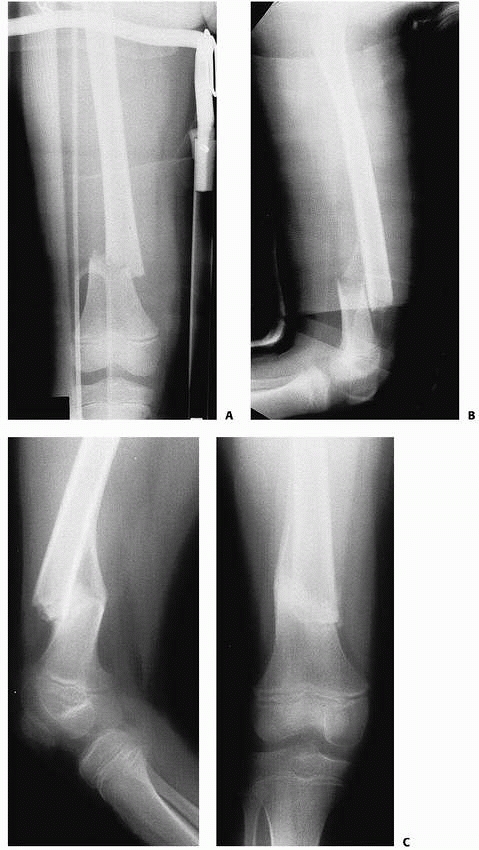

![]() |

FIGURE 22-2 A. Femoral fracture through a poorly demarcated mixed, osteoblastic, osteolytic lesion—an osteosarcoma. B. Sclerotic borders of this lesion in the distal femur are typical of a pathologic fracture through a nonossifying fibroma.